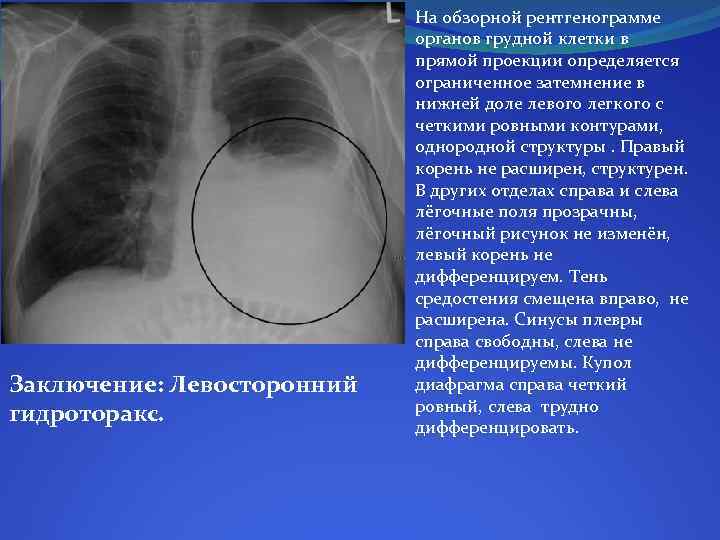

Диагностика плеврального выпота: что нужно знать